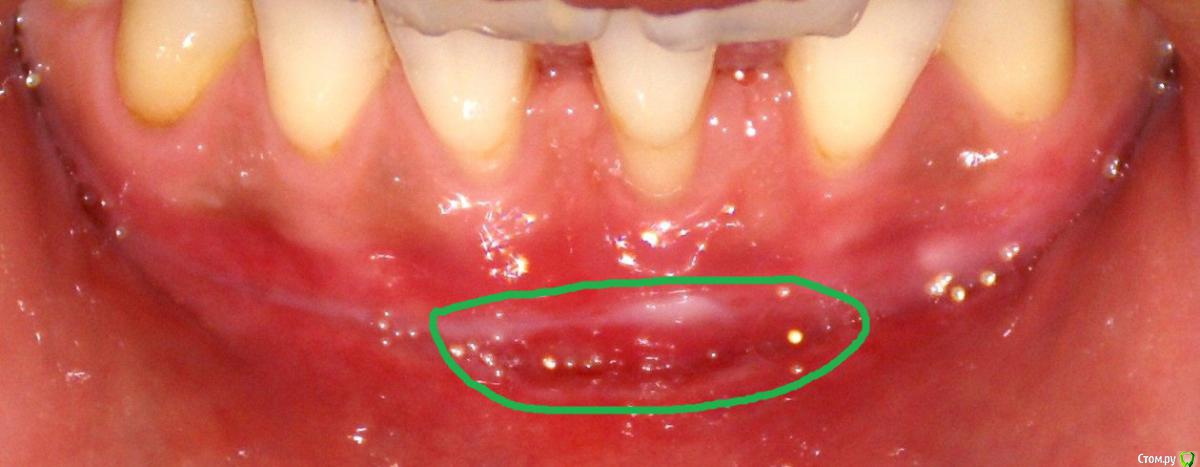

Irina_S Опубликовано 15 июня, 2017 Поделиться Опубликовано 15 июня, 2017 Здравствуйте, уважаемые специалисты! Заранее прошу прощения за не слишком качественные фото! Почти восемь месяцев назад мне была сделана вестибулопластика на нижней челюсти.За пять дней до операции ситуация во рту выглядела так: Для проведения операции были такие показания: Вот ещё описание самой операции, которая была 24 октября 2016 г.: Через шесть дней после операции: Ещё через шесть дней, 5 ноября: Прошла ещё неделя, 12 ноября: Следующий раз фото, к сожалению делалось через три с лишним недели, 4 декабря, в разных ракурсах: После этого визуальные изменения касались только уменьшения белёсых мест от разреза.Вот состояние на 10 июня этого года с разными вариантами оттягивания губы: По результатам заживления я не вижу разницы в глубине преддверия, ради чего и проводилась операция.К тому же всё время с момента операции присутствуют стягивающие ощущения и ощущение инородного тела в подбородке. Ответьте, пожалуйста, правильно ли была сделана операция вестибулопластики?Спасибо за внимание! Ссылка на комментарий

колесников Опубликовано 15 июня, 2017 Поделиться Опубликовано 15 июня, 2017 По уровню прикреплённой десны ситуация выглядит лучше,стабильнее чем до вмешательства. После вмешательств такого рода часто случаются рецидивы и неудачи,у Вас их нет. Но случаются и побочные "осложнения",в частности у Вас образовались тяжи в области клыков,которых раньше не было. Запргнозировать их оборазование зачастую невозможно. Это мягкие ткани,их можно попробовать "растянуть" или размягчить,делая миогимнастику,(надувая пузырь под губой),если это не поможет,дополнительная пластика по устранению этих тяжей. Ссылка на комментарий

Irina_S Опубликовано 16 июня, 2017 Автор Поделиться Опубликовано 16 июня, 2017 у Вас образовались тяжи в области клыков,которых раньше не было. А можно Вас попросить уточнить, что Вы называете тяжами?Под номером 1, под номером 2 или и то и другое вместе? Ещё вот такая хронология: 24 октября была сделана вестибулопластика, 28-го сняли швы, до 13 ноября я касалась кончиком языка "кармана" в глубине линии разреза, отметила это на фото, чтобы было понятно, о чём речь. 14 ноября проводилась обработка зубов с помощью аппарата Вектор и были заложены саморассасывающиеся лечебные повязки на обе челюсти, в том числе и в этот "карман". В этот день увидела, что "карман" визуально склеился из-за заложенной повязки, и я перестала на несколько дней делать упражнения с надуванием губ и касанием кончиком языка.А потом этот "карман" исчез и в итоге получилась поверхность, обозначенная на первой картинке под номером 3. Вопрос: мне не надо было допускать срастания двух поверхностей слизистой, чтобы этот "карман" остался, или его исчезновение и должно было произойти в процессе заживления? (думаю, что это срастание и вызвало ощущение стягивания и уплотнения внутри подбородка в виде инородного тела) Ссылка на комментарий